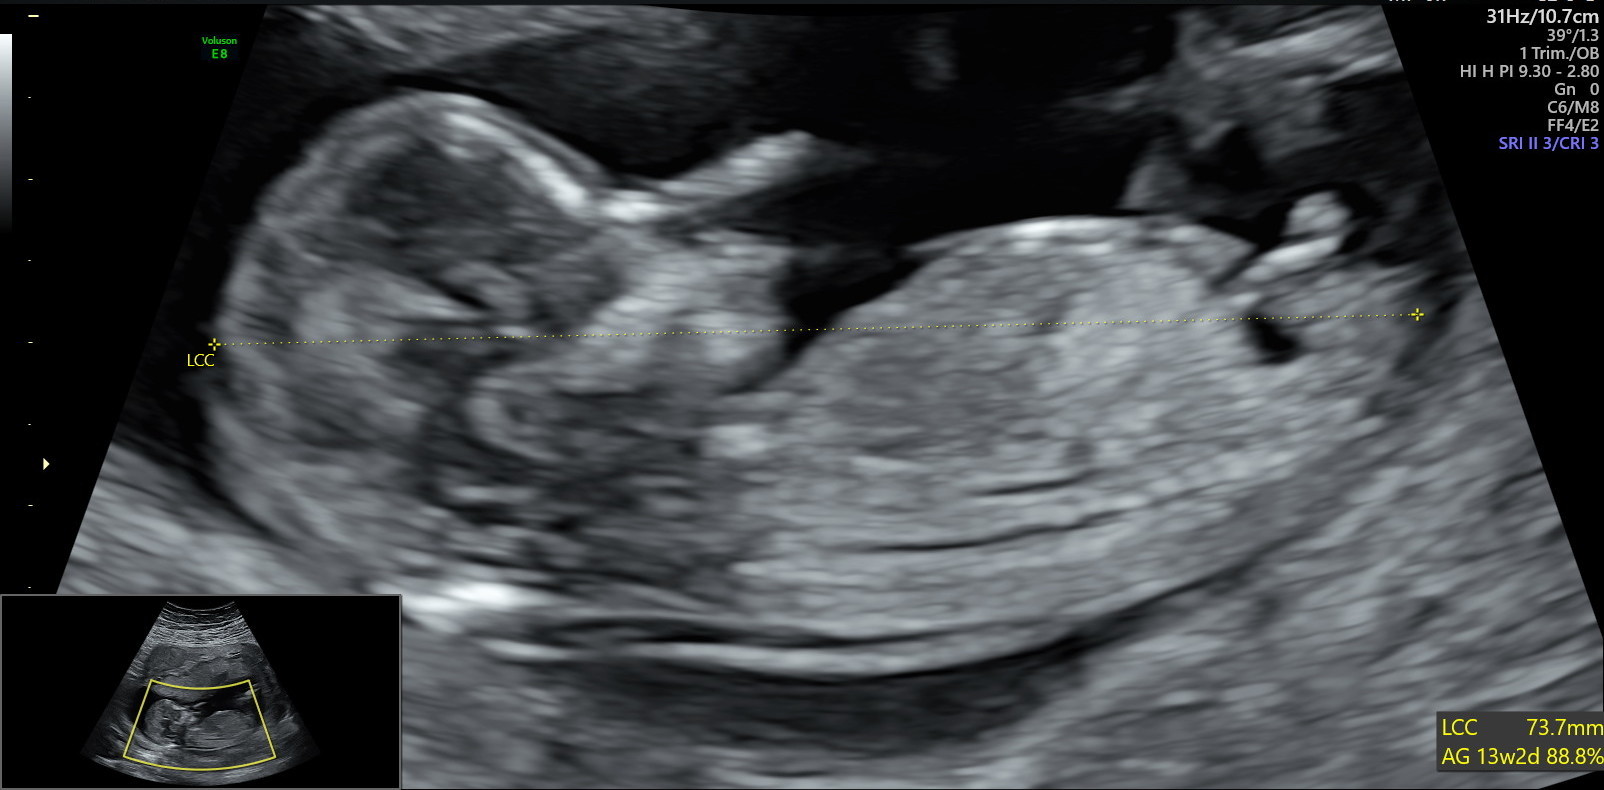

Estil possible de choisir le sexe de bébé?Echo Show 8 (1st Gen, 19 release) HD smart display with Alexa – Unlimited Cloud Photo Storage – Digital Photo Display Charcoal Amazon $ $ 109 99 (238,125)Ainsi dans de bonnes conditions techniques (échographiste entrainé, échographe performant et adapté à l'échographie de grossesse, bon passage des ultrasons à travers la paroi maternelle, bonnes positions du foetus et surout terme de grossesse supérieur à 12,5 SA), le diagnostic du sexe foetal est possible dans plus de 90 % des cas au premier trimestre

Analyser son échographie pour connaître le sexe de bébé Il vous faut donc passer l'échographie T1 (entre 11 et 13 semaines d'aménorrhée) pour avoir des éléments de réponse C'est généralement un grand moment dans votre calendrier de grossesse, émouvant pour les parents, car le fœtus commence à ressembler à un bébéLes envies peuvent également indiquer le sexe du bébé Quand on a envie de manger des produits sucrés, comme du chocolat, des biscuits, ou des bonbons, c'est une fille à l'intérieur du ventre Si l'on opte plutôt pour des frites ou n'importe quelle autre forme d'apéritif salé, c'est un garçonLa 1ère chose qu'elle nous a demandé, c'était de savoir si on voulait connaitre le sexe de cookie En France, il avait fallu qu'on demande au gynéco (un vieux monsieur un peu bourru) à la fin de l'examen pour savoir pour Mlle E lors de cette écho

Je passe ma dernière echo dans une semaine, j'espère que c'est toujours une fille parce que vu plus bas, ça fout le trouille et je crois que j'aurais un gros choc si on me disait maintenant que c'était un ptit gars!Fille ou garçon, le sexe de bébé en question Le sexe de votre futur bébé est déterminé génétiquement dès la fécondation Comment ça marche?On dit souvent qu'il faut attendre l'échographie morphologique du 2e trimestre pour découvrir le sexe de bébé Mais en réalité, si vous avez la bonne image, et si bébé n'est pas trop petit, il est tout à fait possible de vous faire une idée dès l'écho du 1er trimestre

Échographies Le moyen le plus fiable de connaître le sexe du bébé est l'échographie"La première échographie se déroule au cours du troisième mois de grossesse entre la 11e et la 13e semaines d'aménorrhéeDans certains cas, le sexe du bébé peutêtre annoncé lors de ce premier examen", explique le Dr Philippe Mironneau, gynécologue etCe matin, nous avons fait notre deuxième échographie Ce matin, après avoir un peu stressé parce que la sagefemme ne disait rien en regardant ce petit cœur battre, elle nous a rassuré en nous disant que tout allait bien pour ce beau bébé de 500 g, qui avait bien poussé Ce matin, nous avons appris qu'une petite fille viendraitRevelation du sexe de bebe , on attend c'est le grand jour, on connait enfin qui se cache dans mon ventreNous sommes des futurs parents comblé♡ Abonne to